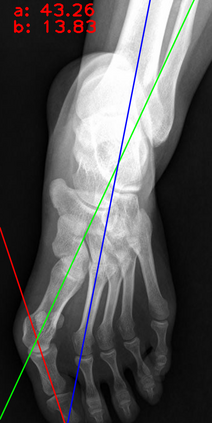

Angular measurements is essential to make a resonable treatment for Hallux valgus (HV), a common forefoot deformity. However, it still depends on manual labeling and measurement, which is time-consuming and sometimes unreliable. Automating this process is a thing of concern. However, it lack of dataset and the keypoints based method which made a great success in pose estimation is not suitable for this field.To solve the problems, we made a dataset and developed an algorithm based on deep learning and linear regression. It shows great fitting ability to the ground truth.